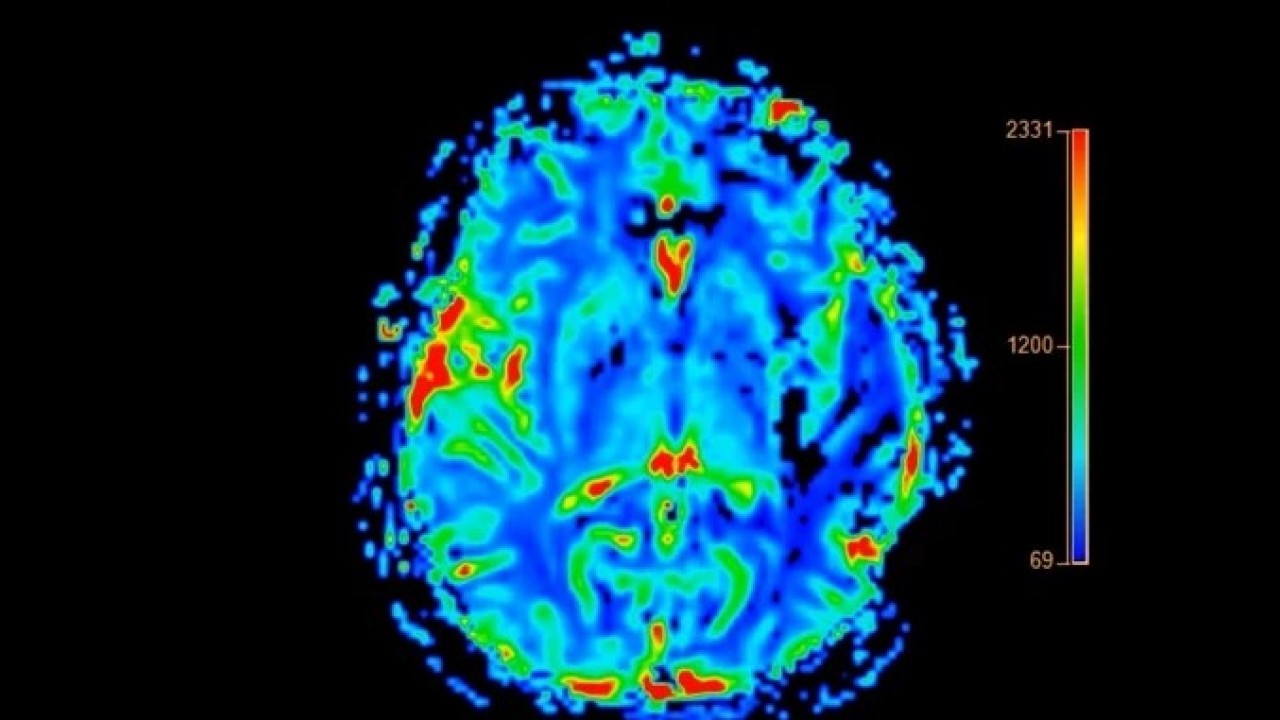

Alzheimer’dan farklı belirtilerle ilerleyen Lewy cisimcikli demans, halüsinasyonlardan ani dikkat değişimlerine, hatta “öne eğilme” gibi ilginç duruş bozukluklarına yol açıyor. Uzmanlar, bu hastalığın çoğu zaman fark edilmediğini ve teşhis geciktikçe yaşam süresinin kısaldığını vurguluyor. İşte Lewy cisimcikli demans hakkında şaşırtıcı detaylar...

Demans türleri arasında Alzheimer en yaygın olanı olmaya devam ederken, daha az bilinen ancak dikkat çekici belirtilerle seyreden bir tür daha var: Lewy cisimcikli demans (LBD).

Uzmanlara göre, bu hastalık Alzheimer’dan farklı olarak özellikle duruş bozuklukları ve halüsinasyonlarla kendini gösterebiliyor.

Michigan Nörolojik Bozukluklar Enstitüsü’nden (MIND) Dr. Jonathan Fellows, LBD ile Alzheimer arasında belirgin klinik farklar olduğunu söylüyor. Dr. Fellows, “Hastalar bilişsel yeteneklerinde, uyanıklık ve dikkat seviyelerinde saatlik değişimler yaşayabilir. Bu dalgalanmalar LBD’nin ayırt edici özelliklerinden biridir” ifadelerini kullandı.

HAFIZA YERİNDE AMA HATIRLAMAK ZOR LBD hastaları Alzheimer’ın aksine yeni anılar oluşturabiliyor, ancak bu anıları hatırlamakta zorlanıyorlar. Aynı zamanda hastalık sürecinde detaylı görsel halüsinasyonlar ve REM uykusu davranış bozuklukları da sık görülüyor.

TEDAVİ SEMPTOM YÖNETİMİNE ODAKLANIYOR LBD’nin kesin bir tedavisi bulunmuyor. Tedavide kullanılan yöntemler, semptomları hafifletmeye yönelik. Rivastigmin ve donepezil, beyindeki sinir hücreleri arasındaki iletişimi destekleyen ilaçlardır. Bu ilaçlar; hafıza sorunları, dikkat eksikliği ve halüsinasyonlar gibi belirtilerin azaltılmasına yardımcı olabilir.